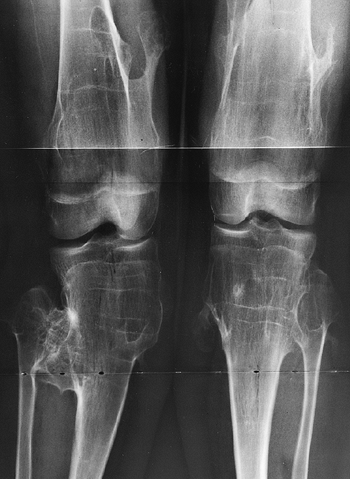

![]() |

Figure 8.14

Lower extremities of a 5-year-old child with chondroectodermal dysplasia, demonstrating the characteristic pronounced hypoplasia of the lateral proximal tibial epiphysis with marked genu valgus. |